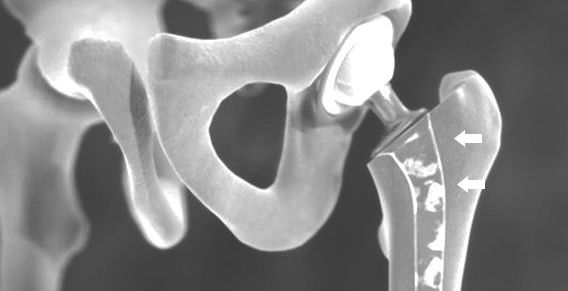

في مفصل الورك، وخاصةً عدوى المادة الاصطناعية ، فإن التلبيد المبكر للعمود أو كسر العظم الذي ينطوي على الغرسات يخشى حدوث مضاعفات.

يمكن إعادة تشغيل OFT باستخدام غرسة الورك الأولية عند استبدال الطرف الاصطناعي. في بعض الأحيان تكون عمليات زرع المراجعة الخاصة ضرورية أيضًا.